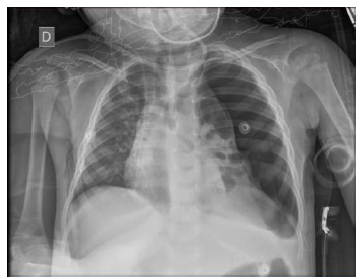

Uma paciente com um ano e oito meses de vida, previamente hígida, no quarto dia de antibioticoterapia com penicilina cristalina 200.000 UI/kg, para tratamento de pneumonia adquirida na comunidade, evoluiu mantendo febre. Exame físico: regular estado geral; descorada 2+/4; FR de 50 ipm; FC de 120 bpm; afebril; PA de 80 x 50 mmHg; sat. de O2 de 92% em nebulização; MV presente bilateralmente, abolido em !$ \dfrac {2} {3} !$ inferiores de hemitórax esquerdo, com broncofonia diminuída nesse local; BRNF em dois tempos, sem sopros; abdome sem alterações; e boa perfusão periférica, sem edema e sem cianose. Radiografia de tórax: condensação em !$ \dfrac {2} {3} !$ inferiores de hemitórax esquerdo. Ultrassom: derrame pleural moderado.

Realizadas a punção e a análise do líquido pleural, observou-se: 1.060 células/mm3 (75% neutrófilos e 25% linfócitos); proteína 4,8 g/dL; glicose 19 mg/dL; DHL 19.889 U/L; pH 7,0; e cultura positiva para Streptococcus pneumoniae, com concentração inibitória mínima para penicilina de 0,06 !$ \mu !$g/mL.

Apesar de ter indicado a conduta adequada, a paciente precisou de intubação e ventilação mecânica por dez dias.

Após estabilização, foi extubada e continuou seguindo o tratamento internada em terapia intensiva, quando evoluiu subitamente com piora clínica, FC de 170 bpm, FR de 60 ipm, saturando 88% em nebulização, PA de 60 x 30 mmHg e tempo de enchimento capilar de 4 segundos. Realizou nova radiografia de tórax, mostrada abaixo.

Nesse momento, a conduta a ser adotada será